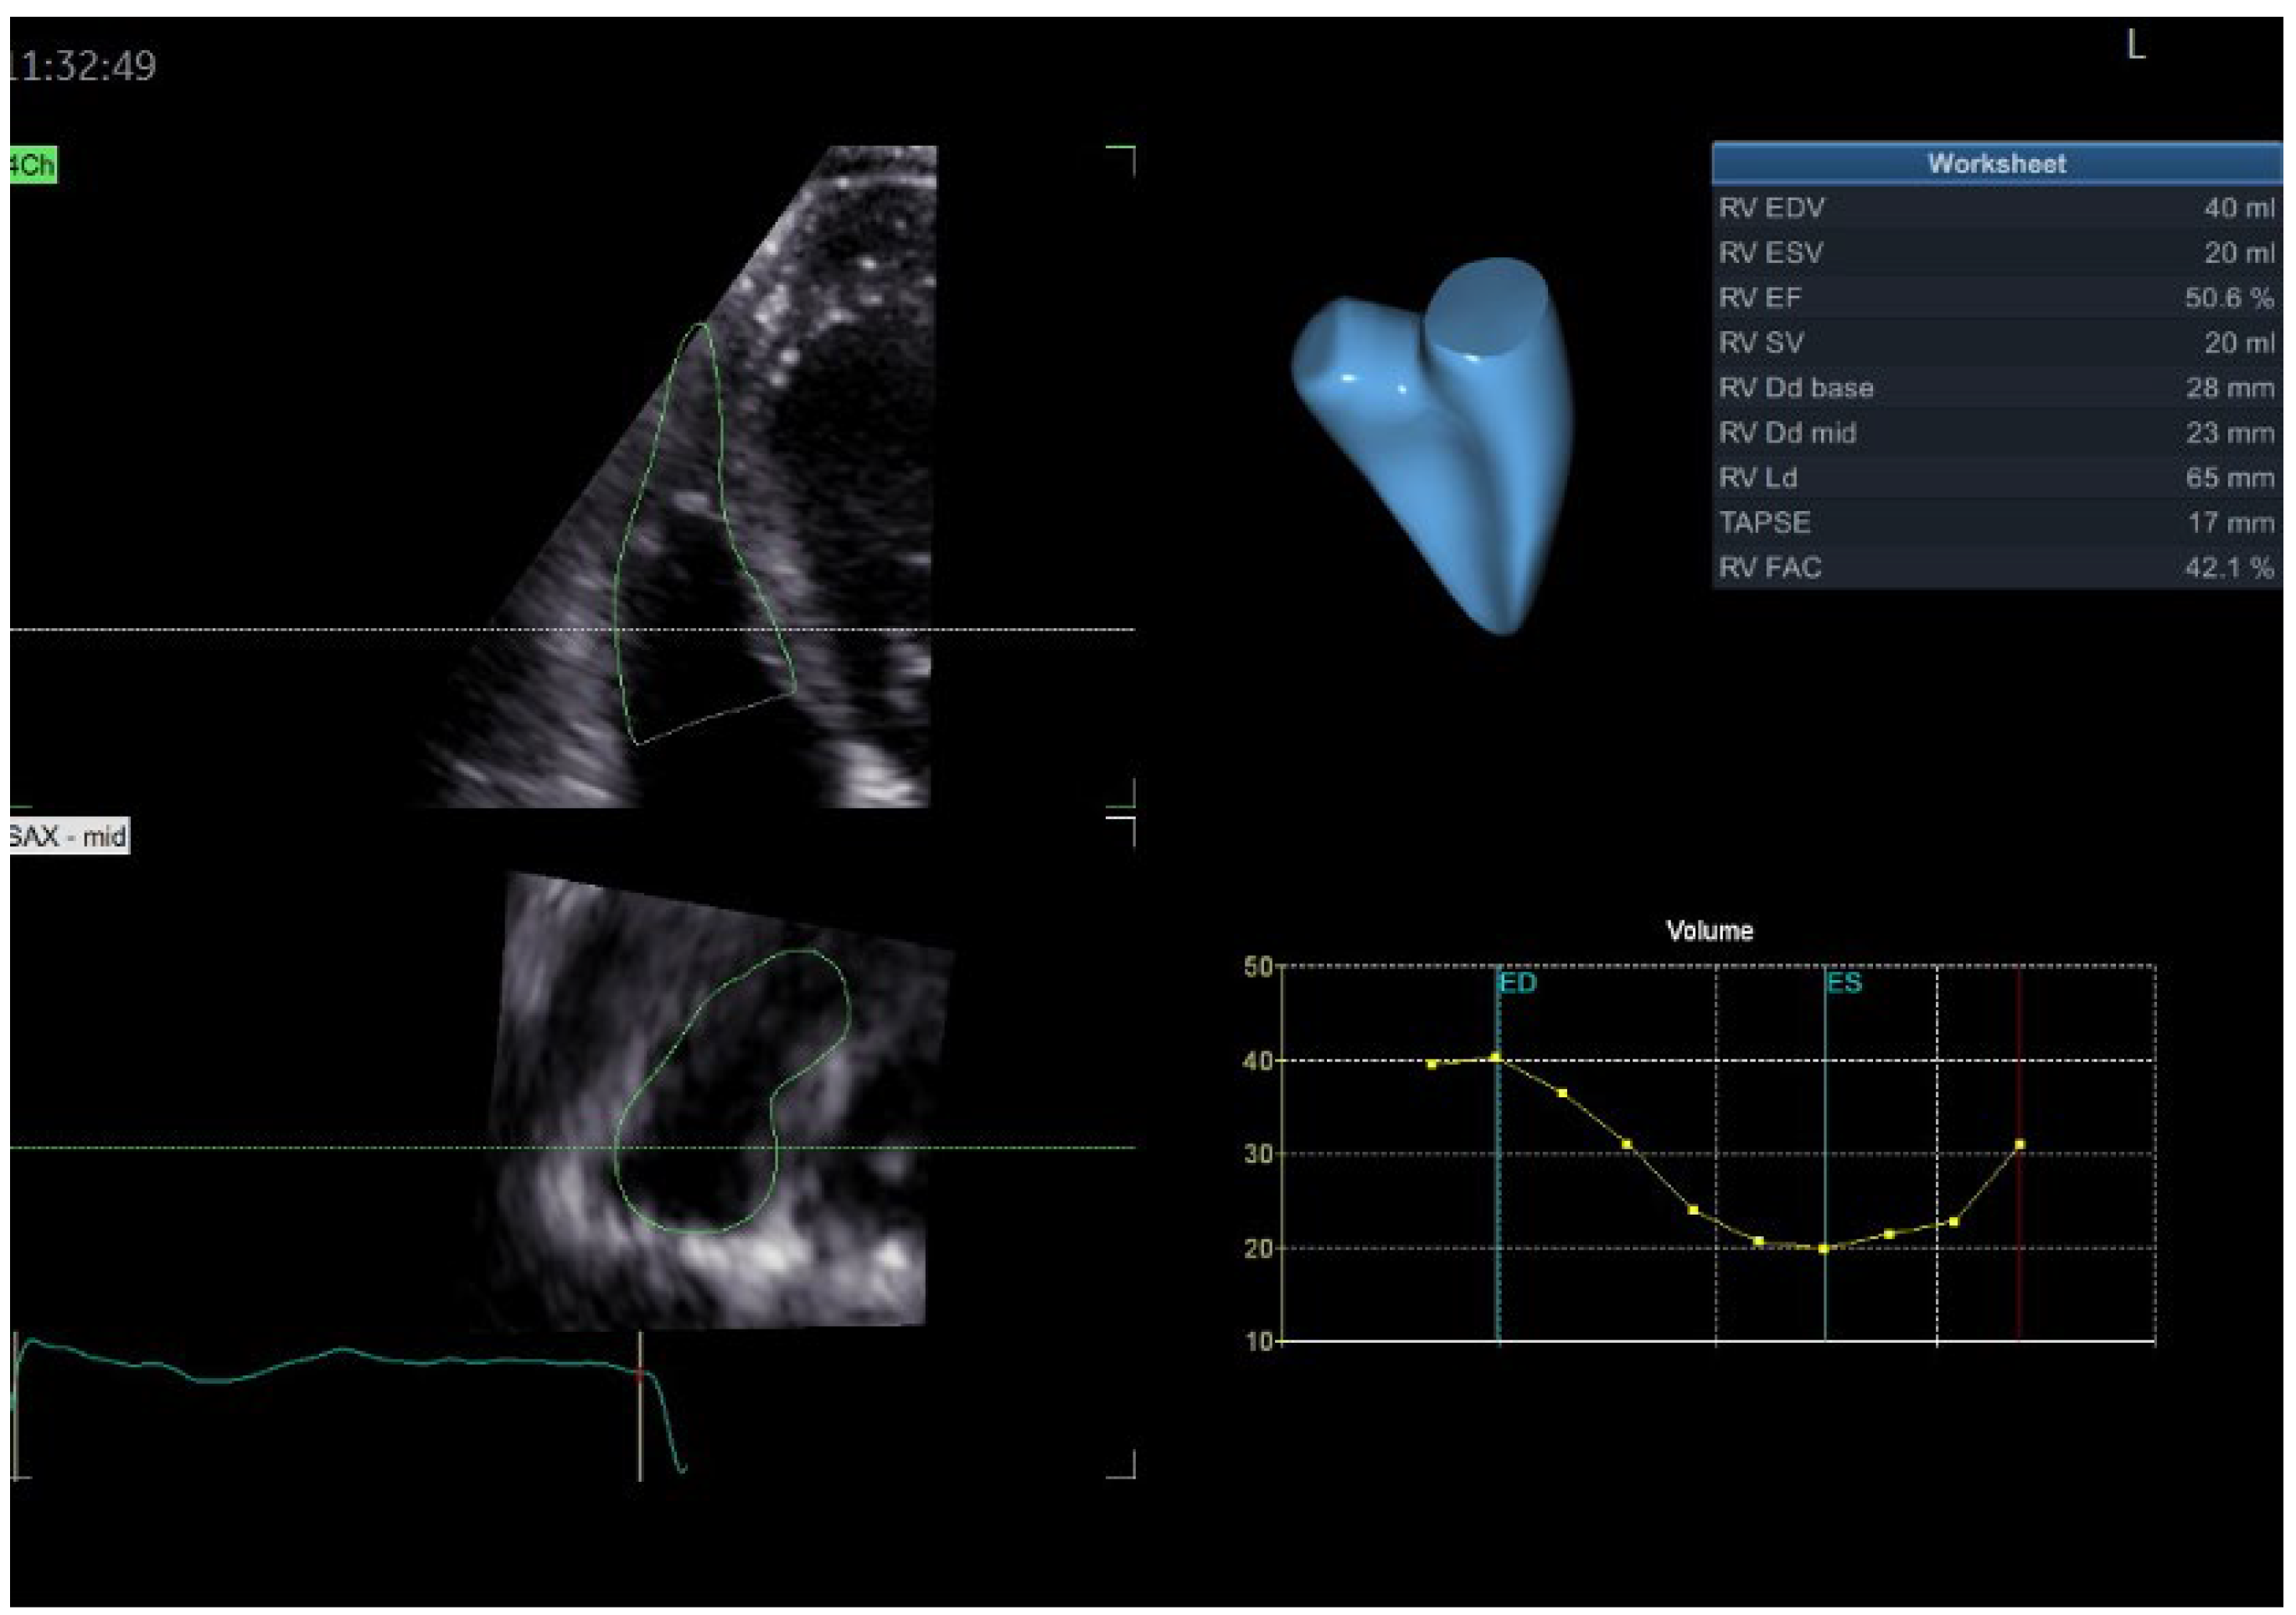

| Echocardiography | Hypokinetic non-dilated cardiomyopathy LVEF = 42% Mild mitral regurgitation IAS aneurysm | Hypokinetic non-dilated cardiomyopathy LVEF = 34% Mild mitral regurgitation IAS aneurysm | Left ventricular concentric hypertrophy LVEF = 54% |

| Cardiac magnetic resonance imaging | Hypokinetic non-dilated cardiomyopathy Left ventricular non-compaction LVEF = 50% | Hypokinetic non-dilated cardiomyopathy Regional sub-epicardial fibrosis LVEF = 41% | Not carried out |